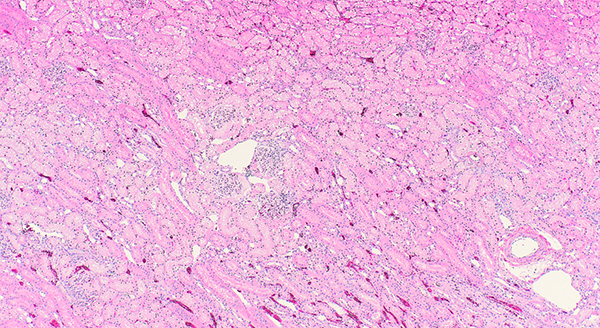

Histology:

A Cornerstone of Diagnostic Excellence at KAHDL

The Histology section is a cornerstone of animal disease diagnostics at KAHDL. Tissue samples submitted in 10% neutral buffered formalin (NBF) whether surgically removed biopsies, tumor masses, tissue samples from field necropsies, or specimens from in‑house necropsies are routed to Histology for processing. These samples undergo several key processes before being returned as slides to the veterinary pathologists for diagnostic evaluation.